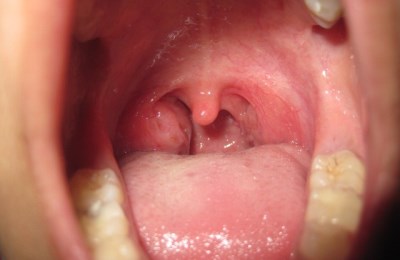

Все эти клетки входят в состав гноя при гнойных поражениях гланд. Расположены небные по бокам перед глоткой в конце ротовой полости. Их расположение можно увидеть на фото.

Различают внутреннюю и наружную (доступную для осмотра) поверхность миндалин. Внешняя поверхность может быть бугристой или ровной, но она всегда выпуклая. У некоторых людей по ним проходит бороздка, из-за которой кажется, будто гланды состоят из двух неравных долей.